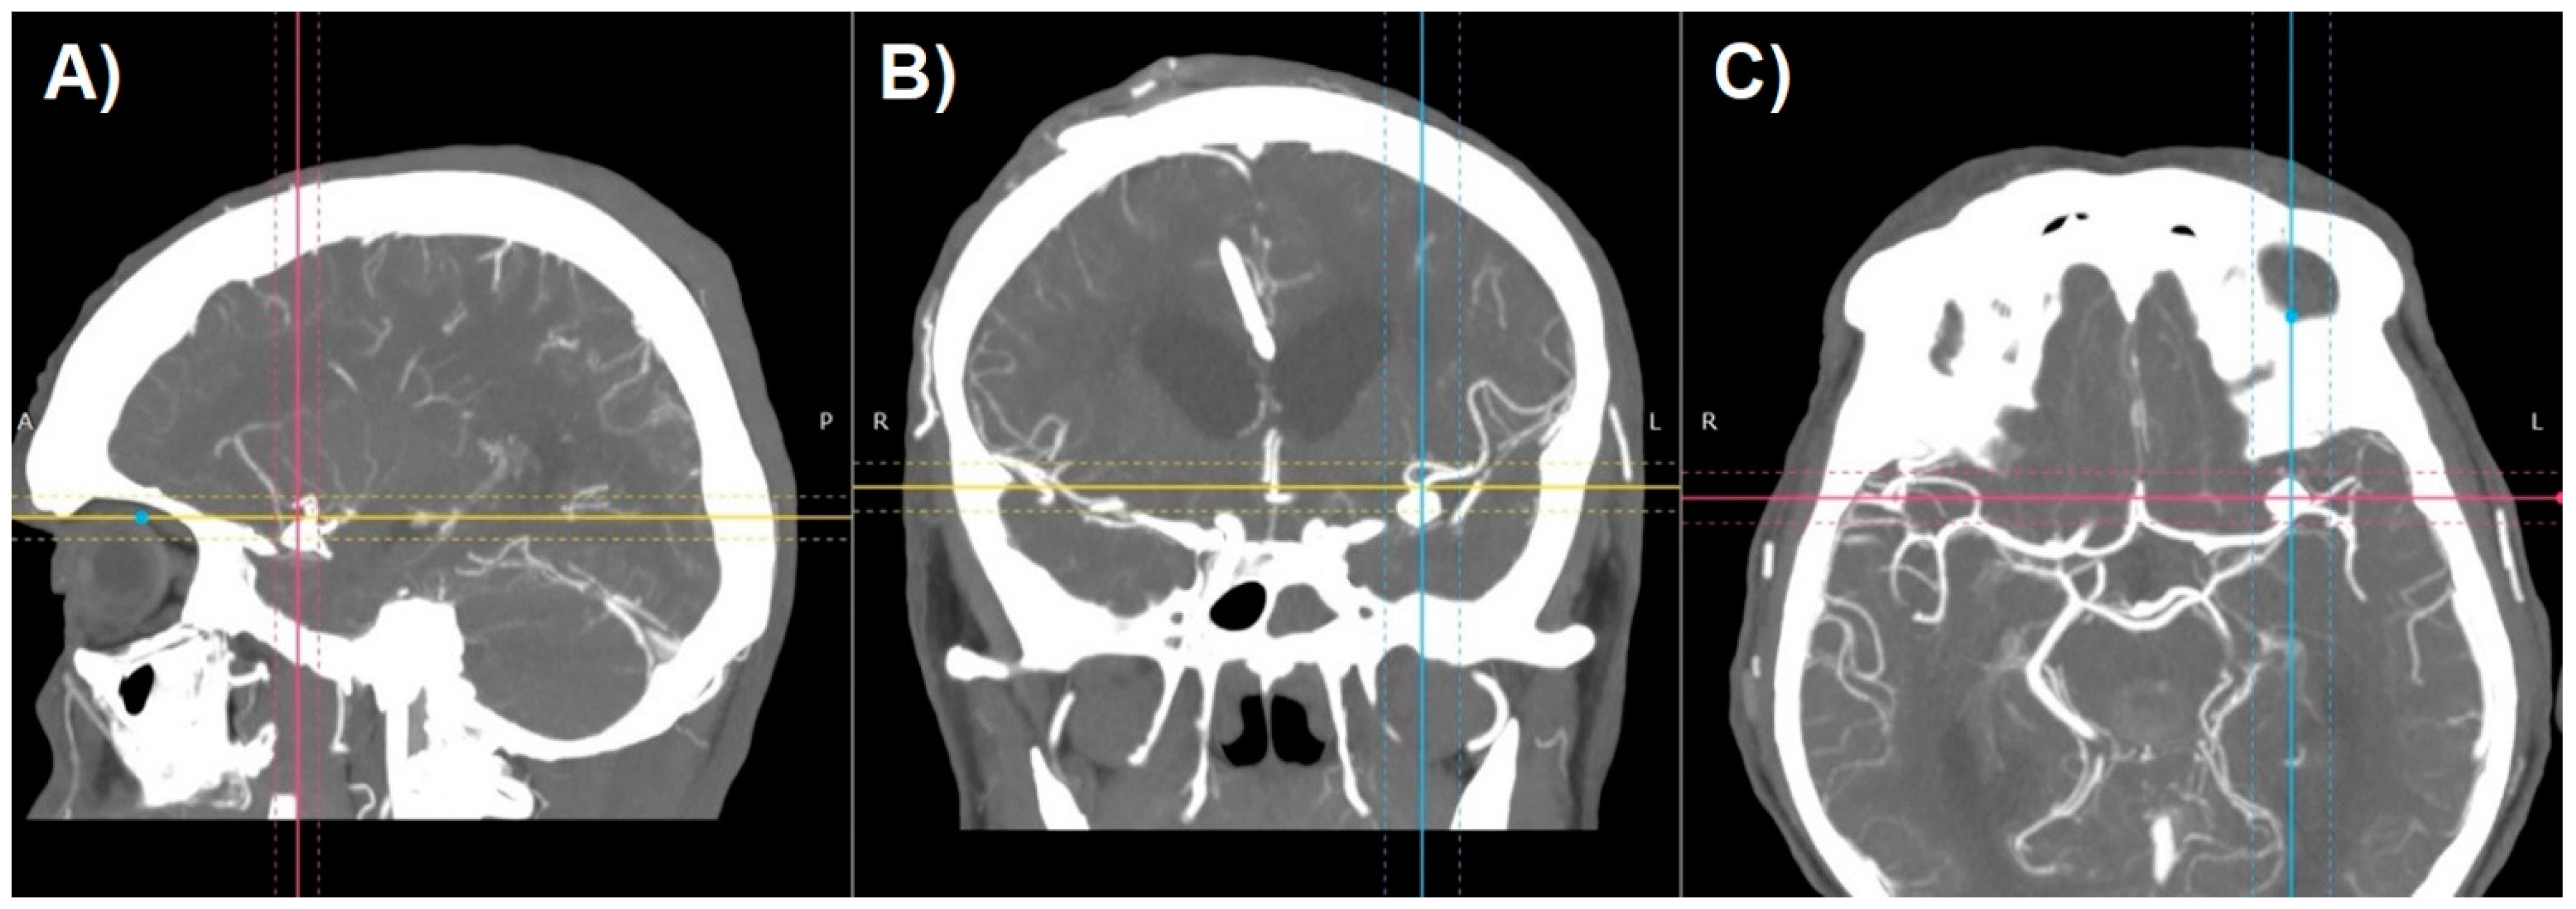

SS-VRT is a technique facilitating the creation of a truly 3D visualization of CT volumetric data for display from any desired perspective (Figure 3) [9]. These techniques typically select voxels to be included in a surface rendering based on a selected range of Hounsfield values. By properly choosing the Hounsfield range, different types of tissues can be outlined like parenchyma, bone, vessels etc. Volume of CT data can be segmented into several of those tissue types according to the combination of Hounsfield ranges. These techniques then calculate the location of surfaces separating tissue types. The surface information is then used to calculate a perspective visualization based on observer position and light source positioning [10]. SS-VRT images provide a sensation of three-dimensionality that seems to be superior to any sort of 2D image, as the model created that way can be rotated, tilted, zoomed in and out, which creates the greatest opportunity to perceive the orientation of treated pathology. Both of aforementioned techniques, however helpful, remain only a two-dimensional presentation of three-dimensional content on the screen.

Figure 3.

Shaded surface display volume rendering technique reconstruction of CT-angiography of patient with cerebral aneurysm: (A) raw reconstruction. (B) Circle of Willis after initial cropping.